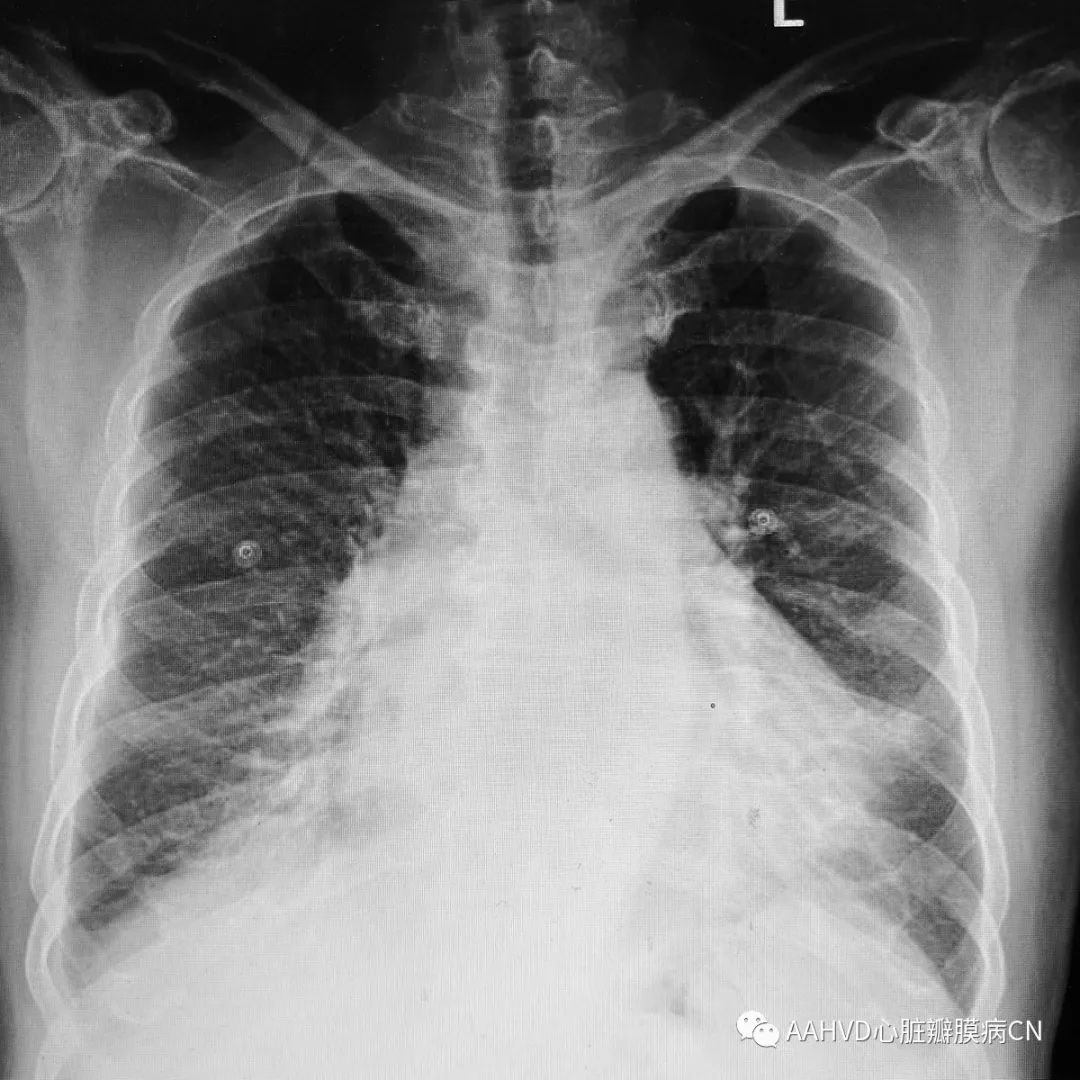

术前胸片

640_2

女性,54岁,主诉:心慌10余年

手术日期:2018年12月19日

术前经胸超声:

风湿性心脏病,二尖瓣返流面积9.7cm²(重度返流),瓣口面积1.0cm²(重度狭窄),E前向流速256cm/s;三尖瓣少量返流。